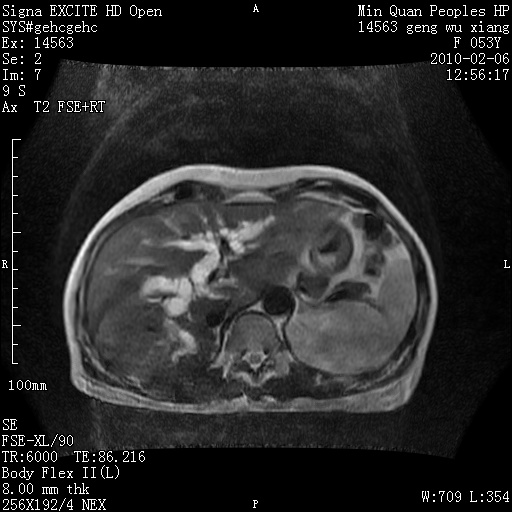

标题: MRI2762:胆道梗阻原因?

f,53y,全身黄染多日。

高位胆道梗阻 胆管癌可能性大

支持 高位胆道梗阻 胆管癌可能性大。